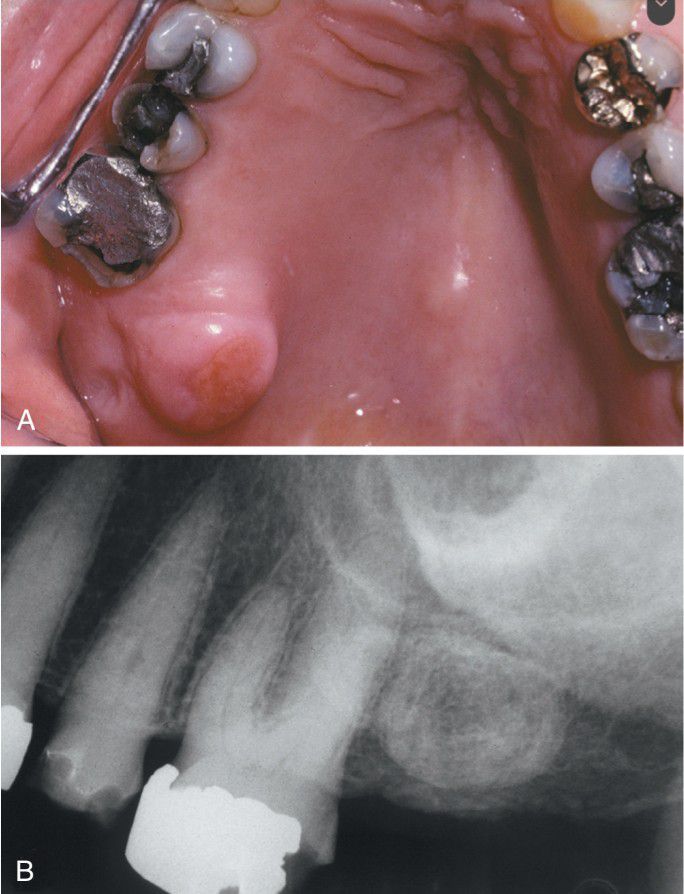

Exostosis

Secondarily ulcerated palatal exostosis. B, Radiograph shows an ovoid radiopacity distal to the molar.